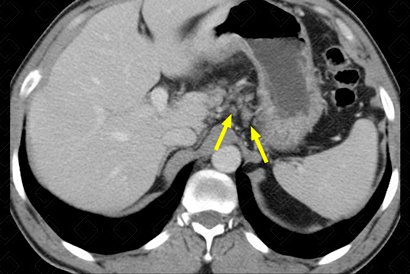

Descrição das figuras: Tomografia computadorizada do abdome pós-contraste, fase portal. Estadiamento de adenocarcinoma gástrico. Na seta vermelha, torna-se evidente o espessamento parietal da mucosa gástrica. As setas amarelas indicam linfonodomegalias em número aumentado na região perigástrica suspeitas.

• Tomografia computadorizada do abdome: Exame extremamente útil para estadiamento da doença, com avaliação da invasão local do tumor e, também, de metástases a distância. Permanece como exame de escolha para estadiamento pré-tratamento e para follow-up da lesão (figuras acima);